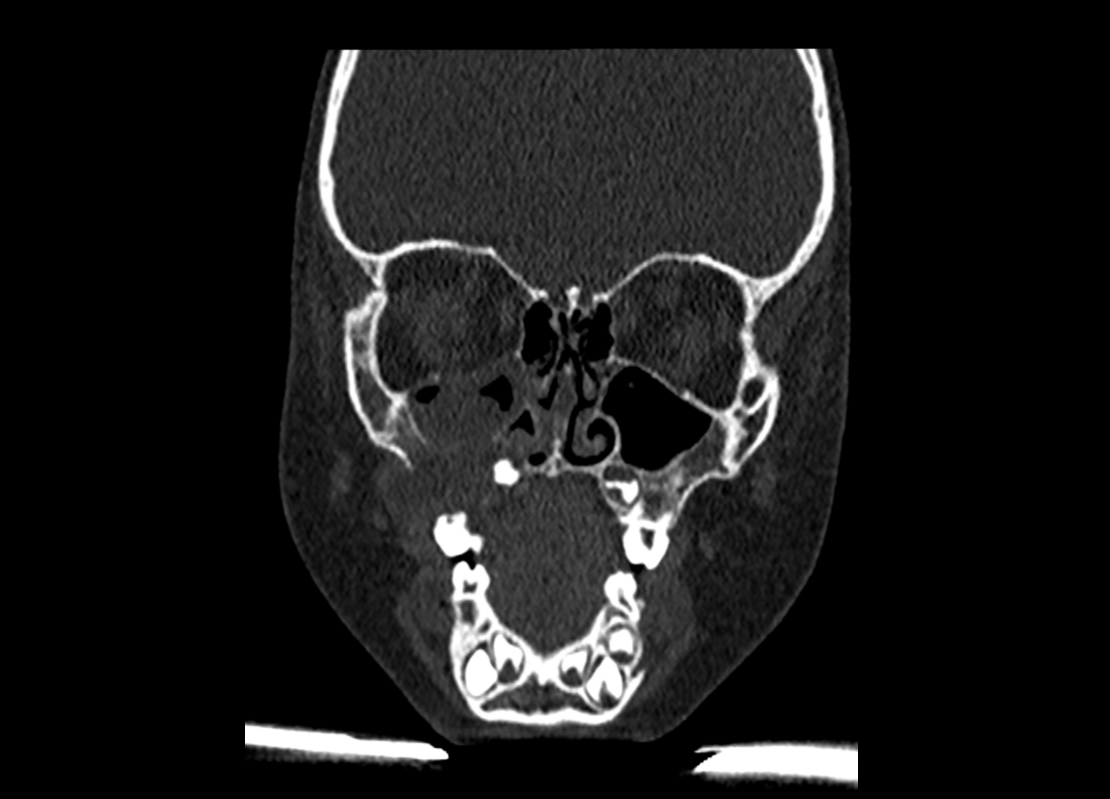

Ante la nueva sospecha diagnóstica se realiza una tomografía computarizada (TC) cráneo-cérvico-toraco-abdominal, en la que se observa una masa en la fosa iliaca derecha y una lesión ósea agresiva maxilomandibular derecha, junto con una adenopatía submandibular ipsilateral.